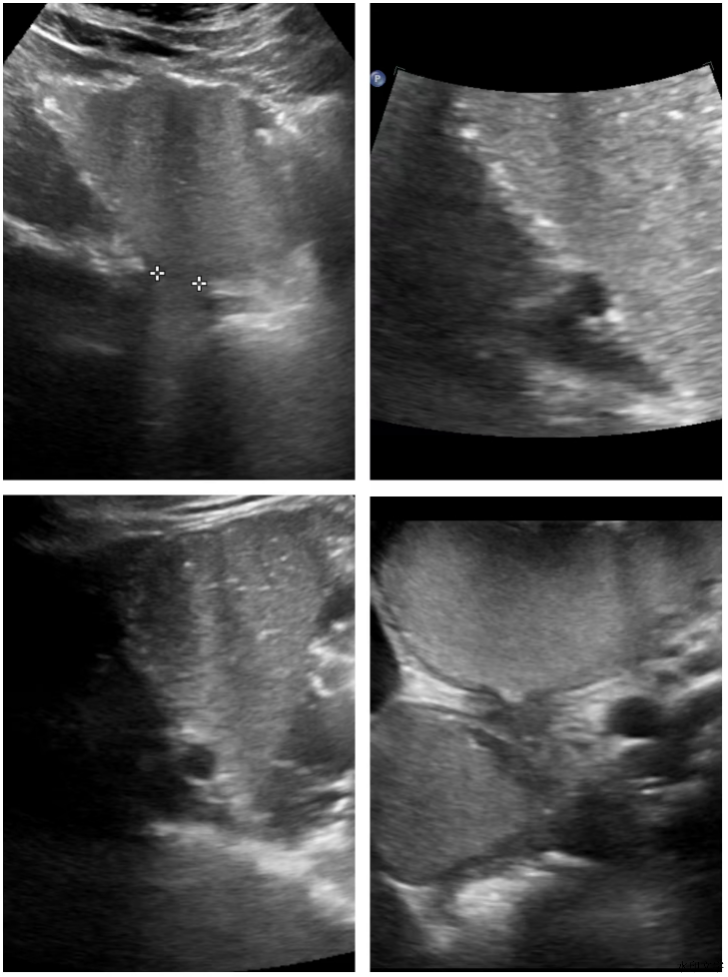

在张新华主任的指导下,我院超声科成功完成了数十例胃肠超声的规范检查,科室医务人员对胃溃疡、十二指肠球部溃疡、胃平滑肌瘤、胃食管反流等疾病能更快速准确地做出诊断,为临床医生的治疗提供重要诊断依据。此次培训的成功开展,不仅提高了我院胃肠超声的技术水平,也加强了超声科与各临床科室间的合作与交流,对有力推动我市胃肠超声技术的持续发展和广泛应用发挥了积极且重要的作用。

3、可清晰显示胃肠壁各层结构,可以看到黏膜下肿瘤生长浸润情况,补充胃镜和钡餐等检查的不足。三者互相结合,可取长补短大大提高了病灶的分辨率和检出率;